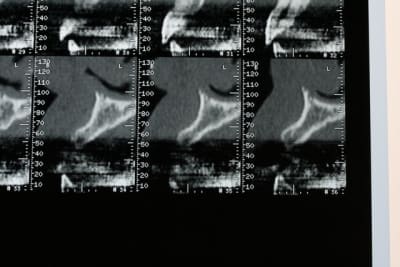

bon, première salve...

photos du scanner...et avec la planche radio pour bien estimer le volume disponible

d'entrée de jeu, on peut se dire que çà va être plus coton pour la 22 que pour la 12 car on à moins d'épaisseur et la corticale est plus dense...